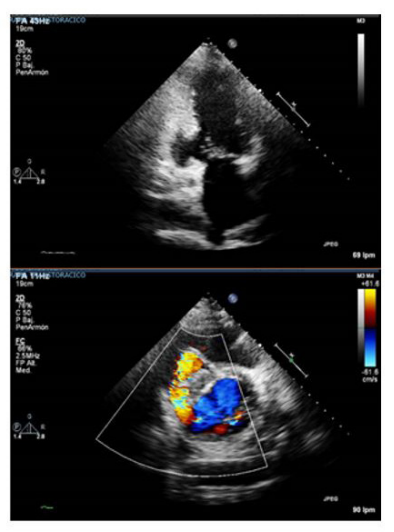

Posteriormente, se le realizó un ecocardiograma que encontró: ventrículo izquierdo levemente dilatado (3,2 cm/m2 ), sin hipertrofia, pero con un aneurisma en el segmento basal y medio de la pared inferior, el cual estaba roto hacia el ventrículo derecho produciendo comunicación interventricular de 2,6 cm, con flujo de izquierda a derecha, sin trastornos segmentarios de la contractilidad, fracción de expulsión calculada con el método de Simpson modificado en 40 %, insuficiencia tricúspidea moderada sin otras anormalidades valvulares, TAPSE: 9 mm (excursión sistólica del anillo tricúspideo, por sus siglas en ingles), con presión sistólica pulmonar: 54 mm/Hg, aurícula derecha dilatada y aurícula izquierda normal, sin trombos intracavitarios y sin derrame pericárdico (figura 2).

Figura 2 Ecocardiograma transtorácico inicial. Aneurisma de segmentos basales en pared inferior y evidencia de defecto del septum interventricular con flujo de izquierda a derecha.